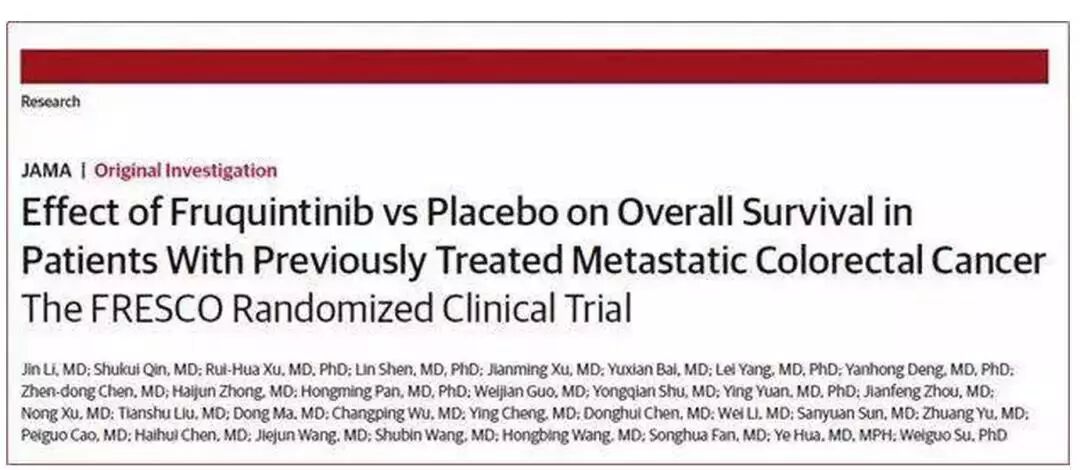

04、中国抗癌创新药临床研究首登JAMA

• 临床突破:2018年6月26日,国际顶尖医学期刊《JAMA》在线全文发表了呋喹替尼三线治疗晚期结直肠癌的随机、双盲全国III期临床试验(FRESCO研究)结果,这是中国自主研发的抗癌创新药临床研究首次刊登JAMA,受到国际医学界的充分认可。目前该药已于今年9月上市,同时也在申请新的适应症如肺癌和胃癌。

• 试验研究:纳入416例既往曾接受至少两线化疗或/和靶向治疗的转移性或晚期转移性结直肠癌患者,中位总生存期(mOS): 9.30 比6.57 个月 ( HR=0.65, P<0.001) ,中位无进展生存期(PFS): 3.71比1.84个月( HR=0.26, P<0.001);总的客观反应率(ORR): 4.7%比0 (P=0.012) ;疾病控制率(DCR): 62.2%比12.3%(P <0.001)。

• 针对疾病:晚期结直肠癌

• 主要研究团队:上海同济大学附属东方医院李进教授,南京中医药大学附属八一医院秦叔逵教授及国内28家肿瘤中心。

• 论文发表:https://jamanetwork.com/journals/jama/fullarticle/2685988